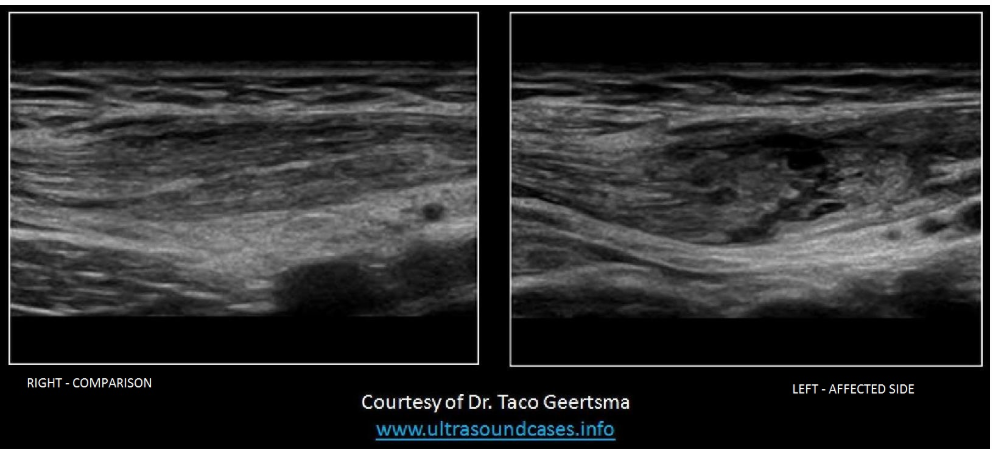

The image demonstrates a transverse view of the right and left side of the abdominal wall, about 5cm lateral to the umbilicus. Which of the following statements is true regarding the findings on the image?

A. There is a heterogeneous, rounded mass located within the left rectus sheath, within the muscle layers and anterior to the peritoneal lining.

The image demonstrates a large hematoma within the rectus sheath of the abdominal wall.